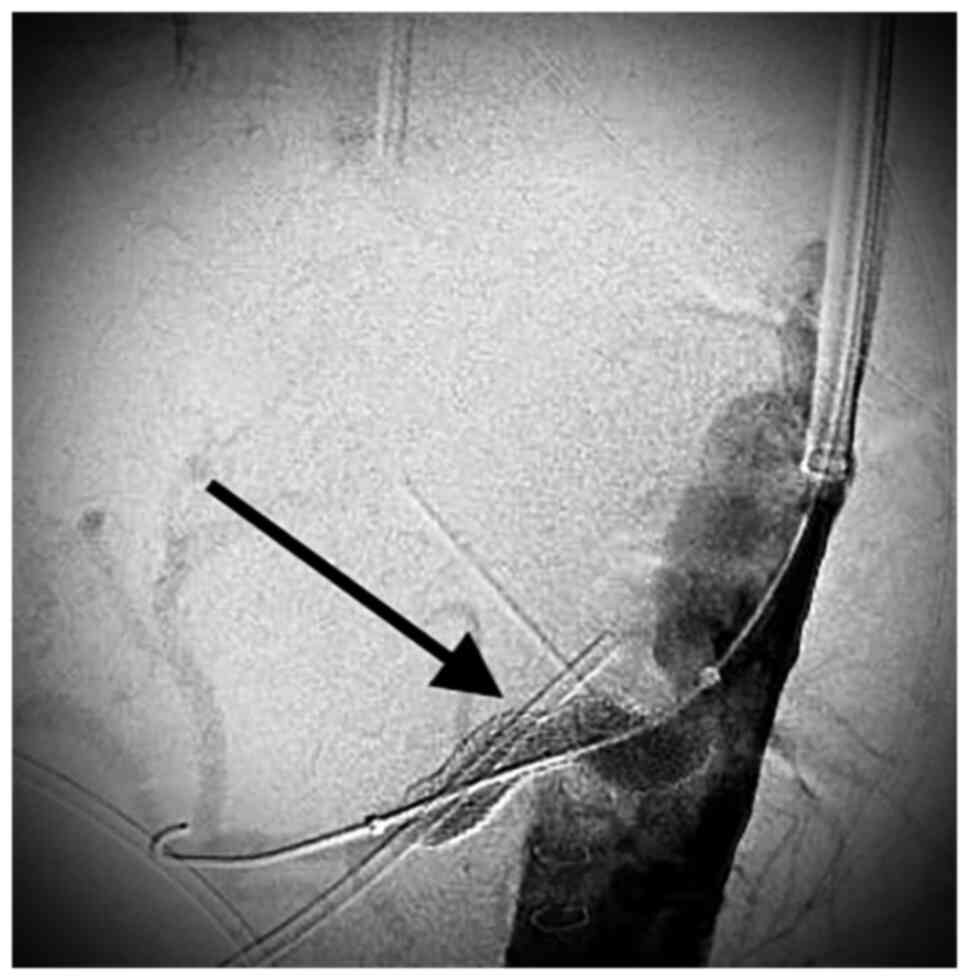

Visceral artery aneurysms are defined in this retrospective analysis as a true aneurysm in the celiac trunk (CT), superior mesenteric artery (SMA), inferior mesenteric artery, and/or their branches. Visceral artery aneurysms (VAAs) are rare and mostly asymptomatic., Rapid growth, size >2 cm, and pregnancy are risk factors associated with rupture. True visceral aneurysms are aneurysms are the result of weakening and thinning of the artery wall. Atherosclerosis, connective tissue disorders, infection (for example pancreatitis) and abdominal surgery are known risk factors for the development of VAA. Nowadays, conservative therapy, endovascular, and open surgery are the treatment options for patients with visceral aneurysms (VAA). During the last decade, endovascular repair of VAAs has been increasingly used (1-6). Catheter-based embolization or stent-graft placement are two major treatment options. Most VAAs originate from the splenic artery (SA) (60%) (Figs. 1 and 2), followed by the hepatic artery (HA) (20-50%) (Figs. 3 and 4). An origin from the superior mesenteric artery (SMA) (6%) (Figs. 5 and 6), the celiac trunk (CT) (4%) or other, smaller visceral arteries is considerably less common (7).

Anastomotic pseudoaneurysms and aortic aneurysms involving the visceral arteries were excluded. The decision to perform an open or endovascular repair was made after discussion in a multidisciplinary meeting (angiology, radiology and vascular surgery). All ruptured VAAs underwent intervention. Open repair was performed in general anesthesia as an aneurysmorrhaphy with or without vascular reconstruction by (direct end-to- end anastomosis or using a vein graft interposition). Endovascular treatment was performed in local anesthesia and consisted either of coilembolization or covered stent placement. If a stent graft placement was technically possible it was performed in order to maintain the vessel patency. If not, a coilembolization was performed.

Six aneurysms of SA, one aneurysm of the CT and one aneurysm of the HA were treated with ER (eight patients). Seven patients were treated with covered stents and one with coiling embolization. In total eight covered stents were implanted. Two patients with SA aneurysms and two patients with SMA aneurysms underwent OS. No allogeneic grafts were required. Three patients needed direct suture only and one a vein graft.